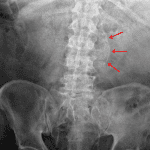

Indication: Abdominal pain

Findings

- Nonobstructive bowel gas pattern

- Infrarenal abdominal aortic aneurysm

- Enlarged cardiopericardial silhouette

- Partially imaged defibrillator lead

Diagnosis

- Abdominal aortic aneurysm

Nonobstructive bowel gas pattern.

Infrarenal abdominal aortic aneurysm. Recommend CT for further evaluation if not previously performed.